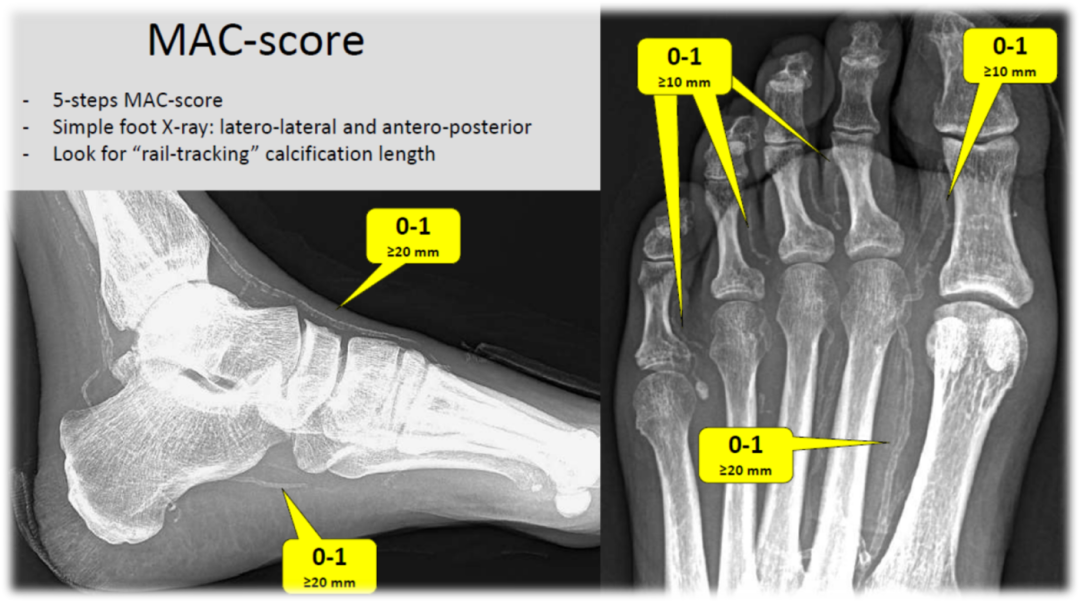

BTK 钙化的 MAC 评分与 SAD 分级

MAC 评分(中膜钙化):通过 5 项问题(如钙化长度≥2cm、≥1cm 等)计分,0-1 分为无,2-3 分为中度,4-5 分为重度;

可视化工具:透视/DSA(评估钙化范围)、超声(检测钙化厚度)、足部 X 线(侧位 + 前后位,观察 “rail-tracking” 钙化长度);